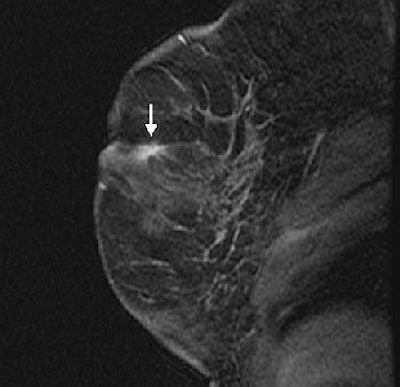

| Same patient as above. Sagittal fat-suppressed T1-weighted, contrast-enhanced MRI on date of MRI-guided needle localization shows persistence of right retroareolar speculated mass (arrow). MRI-guided needle localization yielded 0.5 cm infiltration ductal carcinoma and ductal carcinoma in-situ. Liberman L, Bracero N, Morris E, Thornton C, Dershaw DD, "MRI-Guided 9-Gauge Vacuum-Assisted Breast Biopsy: Initial Clinical Experience" (AJR 2005;185:183-193). |